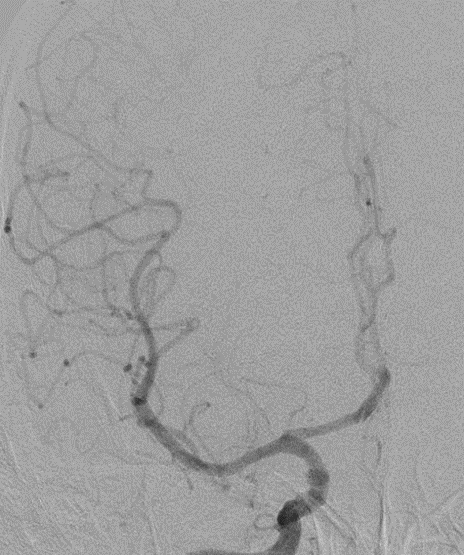

脑血管造影提示右侧颈内动脉颅内段多发动脉瘤(反主动脉弓)

脑血管造影提示右侧颈内动脉颅内段多发动脉瘤

4mm×30mm Streamline

术后4月余随访:多发动脉瘤均未见显影,远端残余轻度狭窄

术前术后对比